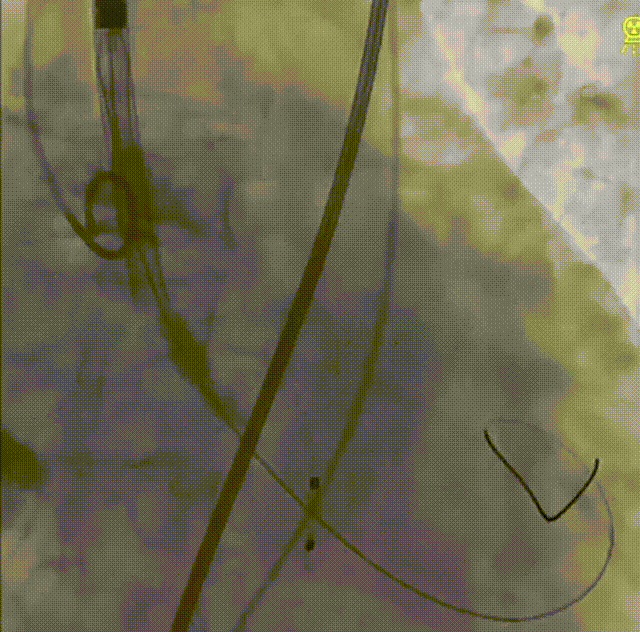

术中经右股静脉穿刺,对主动脉进行血管造影再次确认患者情况,并确定植入支架尺寸。随后,吴文辉教授通过信息采集机器人的高清摄像设备展示了专用于主动脉缩窄的可生长支架CP支架的组装过程,并具体讲解了与之配套的BIB球囊使用方法和效用,该球囊具有双层囊状结构,可均匀扩张CP支架,从而避免形成漏斗形、哑铃形。

CP支架组装过程

顺利完成CP支架组装后,经股动脉放置鞘管,成功将支架和球囊推送至血管缩窄段进行释放,血管造影结果提示预后效果理想。

术前、术后主动脉造影对比